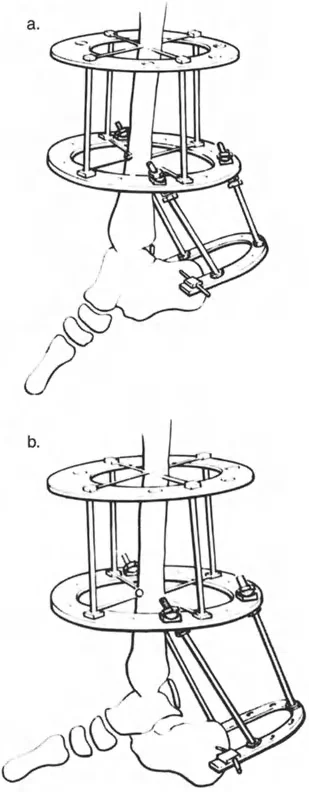

تطويل وتر العرقوب (Achilles Tendon Lengthening)

هذه العملية ضرورية عندما يكون وتر العرقوب قصيرًا ومشدودًا، مما يحد من حركة ثني القدم للأعلى.

- تطويل وتر العرقوب بالشق الجلدي (Percutaneous Z Tendo Achillis Lengthening):

- تُفضل هذه الطريقة في حالات تقوس الكاحل الناتج عن قصر وتر العرقوب فقط، لتجنب التطويل المفرط للوتر.

- يتم إجراء شقوق صغيرة في الجلد وإدخال مشرط خاص (Smillie knife) لعمل شقوق طولية وعرضية في الوتر، مما يسمح له بالتطويل التدريجي مع ثني القدم للأعلى.

- الميزة هي الحفاظ على غمد الوتر سليمًا، مما يساعد على التئام الوتر مع الحفاظ على التوتر.

إزالة النتوءات العظمية وتعميق التلم الكاحلي

في حالات تقوس الكاحل الناتجة عن اصطدام عظمي (Bony Impingement) بسبب نتوءات عظمية في حافة الظنبوب الأمامية أو في التلم الظهري لعظم الكاحل، يقوم الأستاذ الدكتور محمد هطيف بإزالة هذه النتوءات وتعميق التلم الكاحلي للسماح لعظم الكاحل بالثني للأعلى بحرية.

قطع العظم التصحيحي (Osteotomy)

عند وجود تشوهات عظمية مثل تقوس الظنبوب البعيد، قد يتطلب الأمر قطع العظم وإعادة توجيهه. على سبيل المثال، يمكن إجراء قطع عظم قبة ظهرية (Dorsiflexion focal dome osteotomy) في الظنبوب البعيد لتصحيح انحنائه.

تحرير الأنسجة الرخوة (Soft Tissue Release)

إذا لم يتم تحقيق التصحيح الكامل بعد تطويل وتر العرقوب، قد يكون هناك حاجة لتحرير إضافي للأنسجة الرخوة، بما في ذلك اللفافة العميقة الخلفية، وتحرير المحفظة، وتفكيك الالتصاقات داخل المفصل.

- تحرير النفق الرسغي (Tarsal Tunnel Release): يُوصى به وقائيًا في تصحيحات التقوس التي تزيد عن 10 درجات، لتقليل خطر إصابة العصب الظنبوبي الخلفي والأوعية الدم